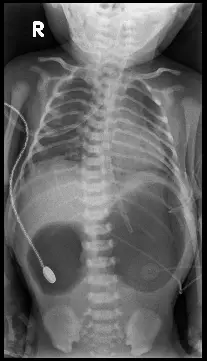

一幼兒因嘔吐求診,腹部X光如圖所示,下列何者為最不可能之鑑別診斷?

新生兒或嬰幼兒胃腸阻塞時,腹部攝影可見“double bubble sign”,即胃與近端十二指腸雙氣泡擴張,提示第二部十二指腸水平的完全性或近完全性梗阻。其鑑別診斷包含:duodenal atresia、duodenal web、annular pancreas、midgut malrotation with volvulus(Ladd’s bands)等;而gastric web(antral web)則位於幽門部,平片表現與上述duodenal obstruction不同。

這張嬰幼兒仰臥腹部AP片,一眼可見:

- 左上腹巨大氣腫泡(胃泡)。

- 胃下方、脊柱右側第二氣泡(擴張的近端十二指腸)。

- 腹腔中下部近乎完全無氣影,無遠端腸道氣體分布。

- 氣管胃管末端在第一氣泡內,符合胃管置入胃部後停留。 此為典型double bubble sign,遠端無氣提示近端完全性梗阻。

- 選項A:gastric web

Antral web是胃幽門部粘膜環狀隔膜,造成胃出口(pyloric channel)梗阻。平片多見單一擴張胃泡(single bubble)並伴gasless abdomen;不會出現第二氣泡代表近端十二指腸擴張的double bubble pattern([pubmed.ncbi.nl